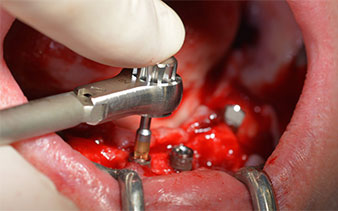

След отстраняване на частичното обеззъбяване в долната челюст, алвеоларният гребен е разкрит от 37 до 47.

Изходът на долночелюстния нерв е първоначално идентифициран като ограничена анатомична структура и, след това, кортикалната кост на гребена е загладена с прав наконечник и голям борер с розовиден профил (Фиг. 4).

Хирургичният протокол за избраните импланти (SKY, bredent medical) изисква обороти от 1,200 rpm за пилотно пробиване с борера (Фиг. 7 - 9).

Това кореспондира със следващата зададена програма на Implantmed. Тук виждаме обратния наконечник на W&H под наклон от 45° ъгъл мезиокаодално в областта на 45, с цел да се предпази менталният нерв. Изходът на менталния нерв е използван като анатомична препратка за всички пробивания в тази зона. Следващите отвори са пробити при намалени обороти от 300 rpm (Фиг. 10 и 11).